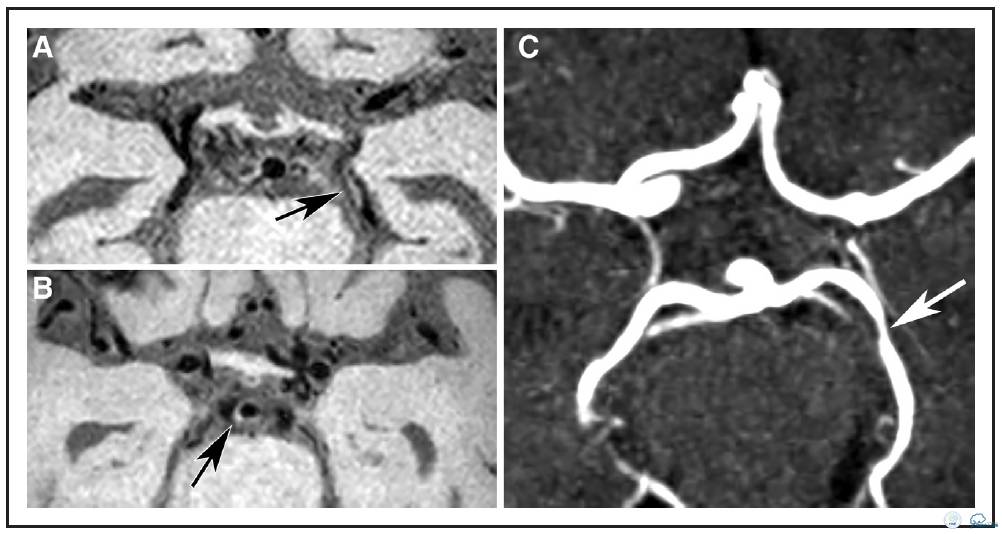

图1:72岁女性患者,左侧前循环梗死。A:横向各向同性的T1加权快速自旋回波采集容积重建图像。B:可见左侧大脑后动脉P2段偏心性,局部增厚病变(箭头),另外,可见基底动脉偏心,局部增厚病变(箭头B)不伴有管腔狭窄(箭头C)。C:横断面时间飞跃磁共振成象显示P2段同一位置为无症状血管壁狭窄病变。

图2:78岁TIA女性患者。A:等中心重建容积采集T1加权快速自旋回波序列成像发现右侧大脑中动脉双侧局部血管壁病变(箭头A),矢状位重建图像(B)右侧大脑中动脉病变(C)显示双侧病变均为偏心性。D:横断面时间飞跃法磁共振血管造影显示对应位置症状性左侧MCA狭窄,无症状性右侧MCA不规则狭窄(箭头D)。